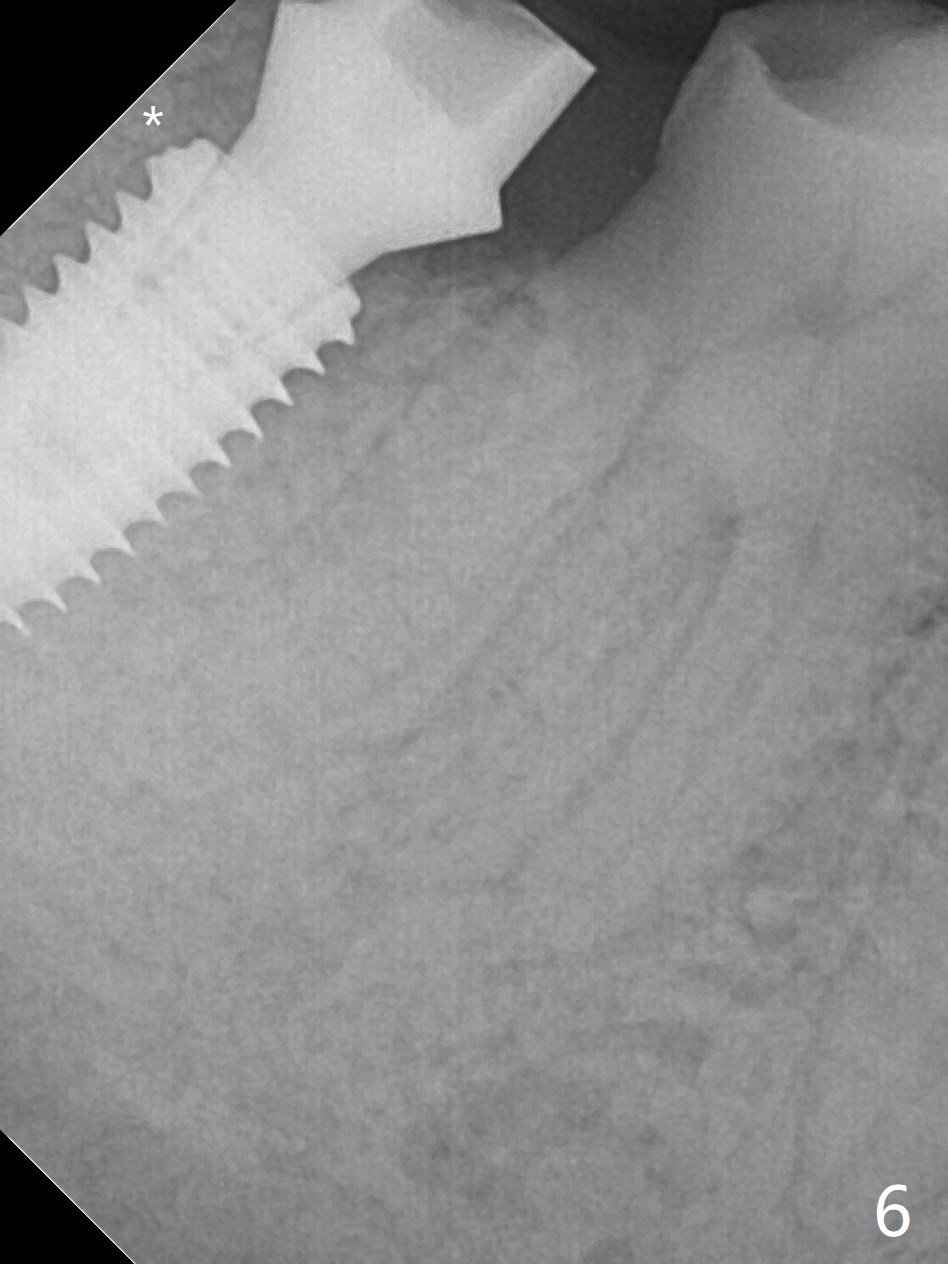

The residual roots of the tooth #31 are lower buccal (Fig.1 B), which in fact is molded and worn by the supraerupted tooth #2. When the tooth is extracted (Fig.2) and an implant, abutment (Fig.3 gold colored) and allograft (*) are placed, the abutment has to be trimmed. An atypical immediate provisional is fabricated by spreading setting acrylic over the abutment and bone graft (Fig.4 P) with occlusal equilibrium. Advantages of the guided surgery are good position (Fig.3 buccolingual), trajectory and depth (Fig.5,6) of the implant. The buccodistally exposed implant threads are packed with allograft in sufficient amount (Fig.3,5,6 *). The atypical immediate provisional breaks down and dislodges 3 weeks postop (Fig.7). In fact the implant plateau is exposed buccally. A monojet is given to the patient for self cleansing. He is instructed to return in 3 weeks. The exposed implant threads are covered 1.5 months postop (Fig.8). Incomplete abutment seating (Fig.9 <) was not noted until 1 year 3 month post cementation when the crown was mobile (Fig.10). A 6x3 mm healing abutment is placed. Three days later, the crown is sectioned and separated from the abutment. The latter returns to place; due to angulation associated with PA, the gap between the implant and abutment is indistinct (Fig.11). Bitewing is taken; the gap exists (Fig.12 <). The abutment seems to be seated deep; there is apparently soft tissue interference. A 5.2x4(2) mm abutment remains incompletely seated (Fig.13 >). A 5.2x4(3) mm one is completely seated (Fig.14 <). Zirconium crown with an access hole is cemented in the mouth. The crown and abutment is then removed for residual cement removal and reseated and torqued (Fig.15). Four months later, the Zirconium crown is fractured (Fig.16). Impression is retaken for high noble metal crown without access hole for strength (Fig.17).